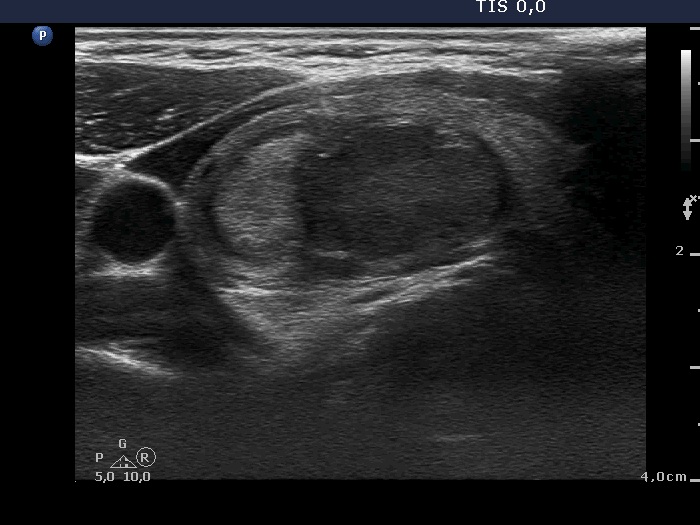

Parathyroid adenoma (histology) - case 671 |

Transverse scan |

Longitudinal scan |

This is a deeply hypoechoic lesion which proved to be a parathyroid adenoma (yellow arrow). The longitudinal images prove that the adenoma was located upper to the thyroid (red arrows). Parathyroid adenomas are almost always hypoechoic.